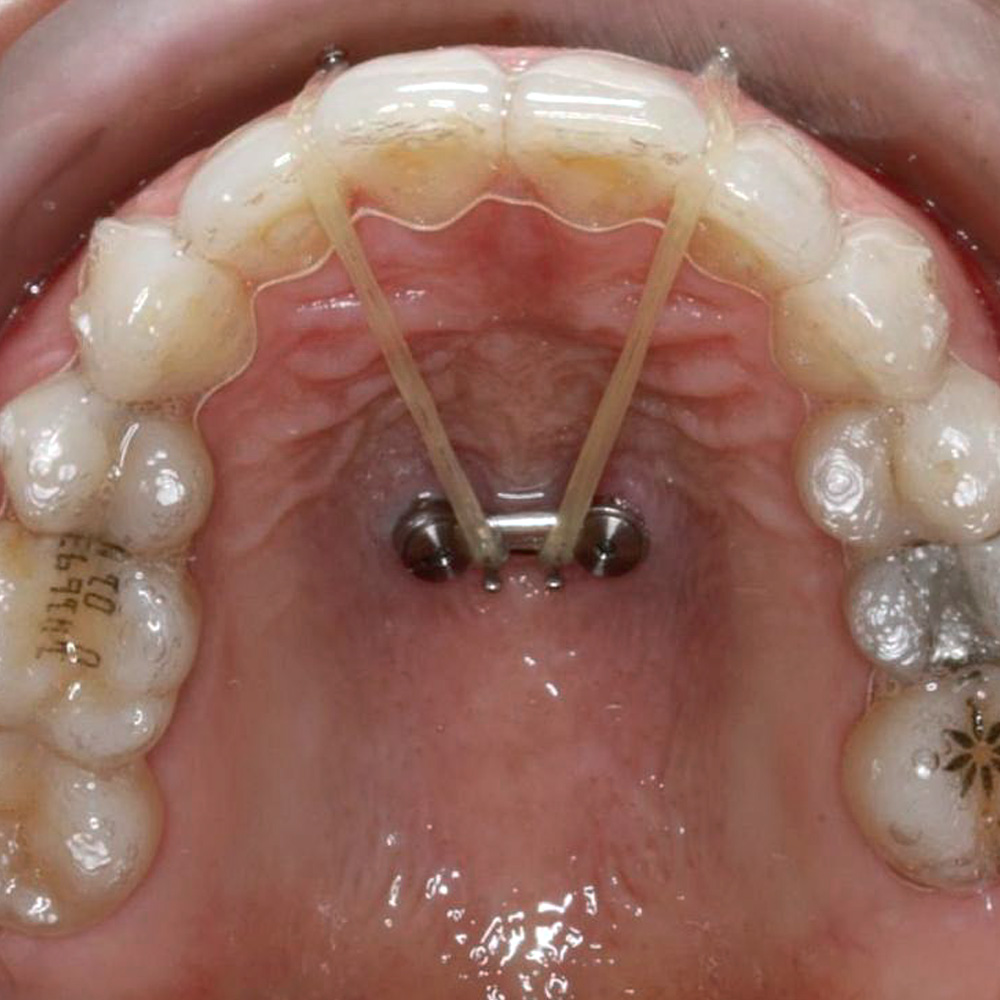

Ce programme de formation dirigé par le Dr Ramón MOMPELL vous offrira une introduction complète à l’utilisation des mini vis en orthodontie, en combinant des sessions théoriques et des démonstrations pratiques. C’est une occasion unique de développer vos compétences avec des praticiens expérimentés.

10h00 – 10h30 : Introduction aux mini vis en orthodontie

• Historique et développement des mini vis en orthodontie • Avantages et indications de l’utilisation des mini vis

10h30 – 11h15 : Biomécanique des mini vis

• Forces et mouvements réalisés avec les mini vis

11h30 – 12h15 : Choix et mise en place des mini vis

• Les différents types de mini vis

• Critères de sélection des mini vis en fonction du cas clinique • Techniques de mise en place des mini vis

12h15 – 13h00 : Planification du traitement avec les mini vis

• Élaboration d’un plan de traitement incluant l’utilisation des mini vis

• Intégration des mini vis dans le plan global de traitement orthodontique

15h00 – 16h00 : Cas cliniques et démonstrations

• Analyse de cas cliniques traités avec succès à l’aide de mini vis • Démonstrations pratiques d’insertion et de retrait de mini vis

16h15 – 17h30 : Démonstration clinique

Démonstration de mise en place de mini vis sur un patient